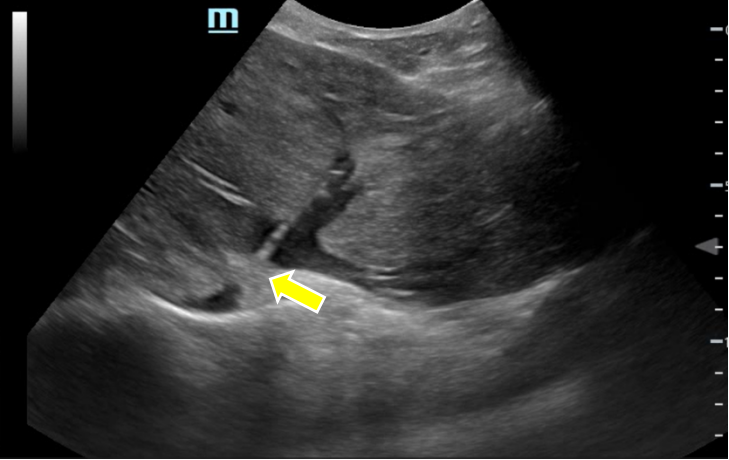

图2 彩超引导下经皮经肝逆行穿刺肝左静脉闭塞处

布加综合征是起源于从肝内的肝小静脉段到下腔静脉和右心房任何一处的肝静脉流出道阻塞。可导致肝衰竭、肝硬化及门脉高压并发症等多种表现。在国内,布加综合征患者以下腔静脉型为主,像李先生这样的单纯肝静脉型病变相对少见。常规介入技术从右侧颈内静脉穿刺入路,经下腔静脉在X光透视下尝试探入肝静脉并进一步扩张狭窄或闭塞的血管部分。李先生肝静脉回流障碍,导致肝脏持续淤血及肝后性门静脉高压,治疗上只需开通一支肝静脉即可解决血液回流障碍。相对而言,肝左静脉开通可能性最大,但是肝左静脉完全闭塞,且走形与肝后段下腔静脉呈垂直关系,导丝及导管无法经下腔静脉“自上而下”探入肝左静脉,而X光透视下无法定位肝静脉准确位置,如果盲目穿刺,下腔静脉及心房破裂出血风险极大。介入手术团队仔细评估患者血管解剖情况,讨论后决定采用超声引导下经皮经肝逆向穿刺肝左静脉闭塞处建立通道来开通肝左静脉。

8月6日,罗薛峰副教授和王小泽副教授为患者进行介入手术。超声引导下以穿刺针经皮经肝穿刺肝左静脉,穿刺针继续在肝左静脉内前进,直至穿过闭塞处进入下腔静脉,谨慎避开心脏。X光透视下推注造影剂明确针尖顺利进入下腔静脉后,将导丝顺着这一通道置入上腔静脉内。然后穿刺右侧颈内静脉,用血管内抓捕器从上而下抓取导丝建立通路,继而引入球囊对肝左静脉流出端进行扩张。经过多次扩张后,复查血管造影可见肝左静脉回流完全通畅,侧枝血管均未再显影。